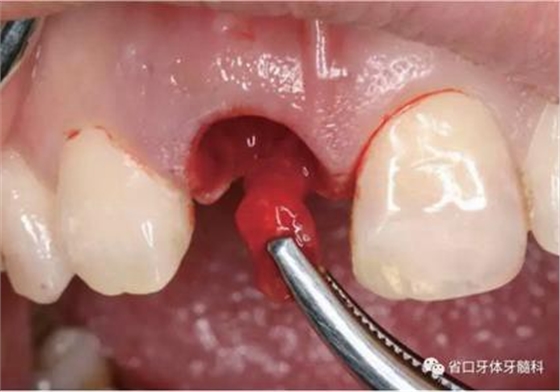

圖7 根尖區(qū)肉芽

圖8 刮除肉芽組織

(1)微創(chuàng)拔牙及即刻種植:術(shù)前拍攝口內(nèi)照及實(shí)施牙周基礎(chǔ)治療。常 規(guī)消毒鋪巾阿替卡因局麻下微創(chuàng)拔除上頜右側(cè)中切牙,搔刮拔牙窩及根尖肉 芽組織。探測牙槽骨唇側(cè)骨壁及鄰面牙槽嵴完整,牙齦無撕裂。不翻瓣下于上頜右側(cè)中切牙缺隙近遠(yuǎn)中中點(diǎn)的腭側(cè)牙槽骨及根方定位,按照逐級預(yù)備的原則,緊貼牙槽窩腭側(cè)骨壁制備種植窩洞,植入Zimer®3.7mm×13mm TSV種植體1顆,植入扭矩>35N·cm,以O(shè)sstell測量種植體的ISQ值為68。 種植體平臺位于唇側(cè)齦緣中點(diǎn)下3mm,與唇側(cè)骨壁內(nèi)側(cè)面形成的跳躍間 隙約2mm,置入Bio-Oss®細(xì)顆粒骨粉0.25g,上愈合基臺關(guān)閉創(chuàng)口。術(shù)后 CBCT檢查顯示:種植體利用牙槽窩根方骨質(zhì)固位,緊貼牙槽窩腭側(cè)骨壁, 其唇側(cè)面與牙槽窩唇側(cè)骨壁的內(nèi)側(cè)面所形成的跳躍間隙(約2mm)可見顆 粒狀顯影物充填。牙槽窩的唇側(cè)骨壁及唇側(cè)倒凹無缺損穿孔。